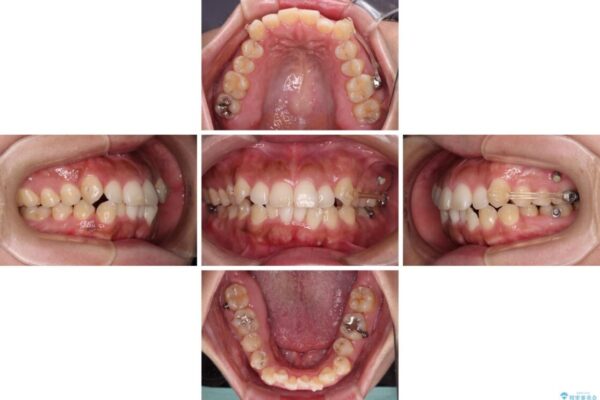

前歯の叢生と八重歯を気にして来院された患者様です。

治療前

• 【モニター】カリエール・ディスタライザーを併用した八重歯のインビザライン矯正 治療前画像